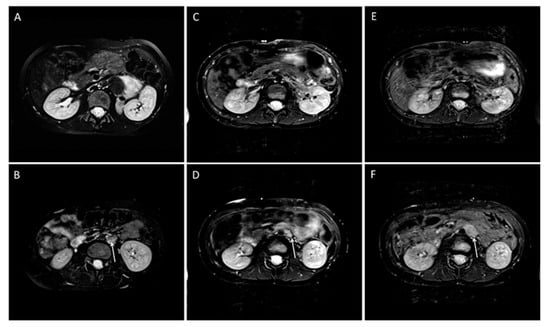

- Gassenmaier, S.; Tsiflikas, I.; Maennlin, S.; Urla, C.; Warmann, S.W.; Schaefer, J.F. Retrospective accuracy analysis of MRI based lesion size measurement in neuroblastic tumors: Which sequence should we choose? BMC Med. Imaging 2020, 20, 105. [Google Scholar] [CrossRef] [PubMed]

- Gassenmaier, S.; Tsiflikas, I.; Fuchs, J.; Grimm, R.; Urla, C.; Esser, M.; Maennlin, S.; Ebinger, M.; Warmann, S.W.; Schafer, J.F. Feasibility and possible value of quantitative semi-automated diffusion weighted imaging volumetry of neuroblastic tumors. Cancer Imaging 2020, 20, 89. [Google Scholar] [CrossRef]

- Trout, A.T.; Towbin, A.J.; Klingbeil, L.; Weiss, B.D.; von Allmen, D. Single and multidimensional measurements underestimate neuroblastoma response to therapy. Pediatr. Blood Cancer 2017, 64, 18–24. [Google Scholar] [CrossRef]